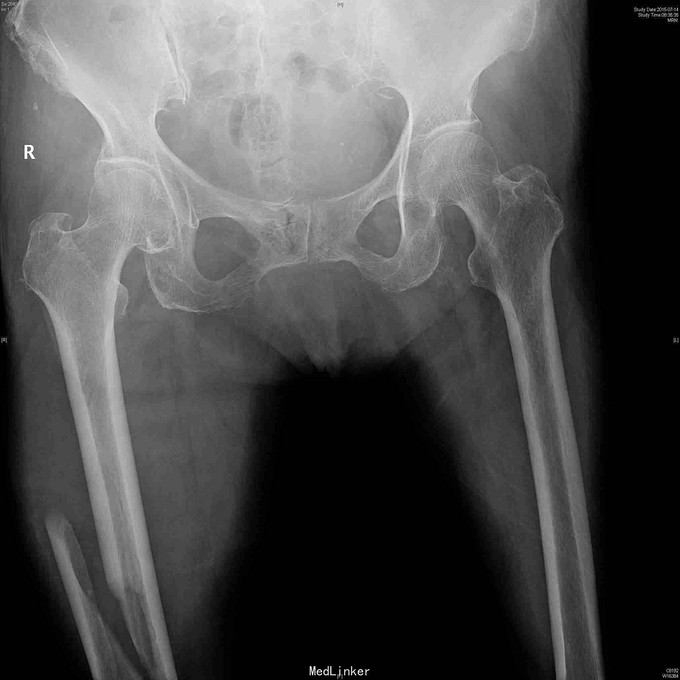

查体:右大腿中下段肿胀明显,淤血,压痛,短缩畸形。小腿感觉正常,足背动脉搏动好。 右股骨正侧位片:右股骨中下段长螺旋形骨折,移位短缩明显。

诊断:右股骨干骨折。 治疗:先行下肢牵引,排除血管神经损伤后,行股骨干中下段螺旋骨折倒打髓内钉技术治疗,术中先行股外侧入路切开用钢丝捆扎复位固定骨折,再穿钉。术后定期拍片复查,预防骨质疏松治疗。